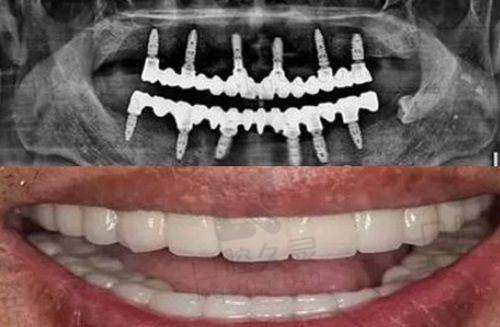

2. 高难度种植技术:擅长处理复杂的种植病例,如all - on - 4、穿颧穿翼等高难度种植,能够为患者提供个性化的种植方案。